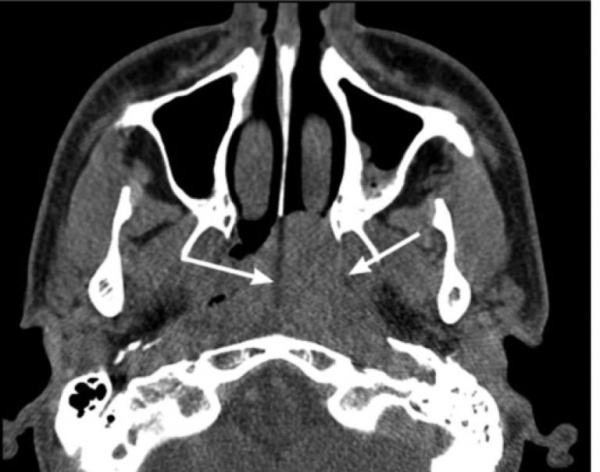

Клиническое наблюдение

Пациент Д., 38 лет, обратился к оториноларингологу в ФГАУ «НМИЦ нейрохирургии им. акад. Н.Н. Бурденко» в апреле 2018 г. в связи с наличием на КТ (от 15.04.18), выполненной в рамках комплексного медицинского обследования, новообразования в передненижнем отделе клиновидной пазухи справа. Пациент отметил, что с юности его беспокоит затруднение носового дыхания, которое он связывал с выраженным искривлением перегородки носа, а также редкие носовые кровотечения, которым он не придавал большого значения, поэтому к ЛОР-врачу не обращался. С целью более детального обследования 25.04.18 была выполнена перфузионная КТ головного мозга, на которой отмечалось наличие объемного образования в основной пазухе и носоглотке с высокими показателями кровоснабжения. Объемное образование активно накапливало контрастное вещество и сбрасывало его в артериальную фазу, в связи с чем нельзя исключить ангиофиброму, однако возраст пациента не соответствовал полученным результатам. С целью уточнения диагноза 14.05.18 пациенту была проведена селективная ангиография, выявившая сосудистую сеть опухоли и кровоснабжение из правой верхнечелюстной артерии (система НСА), что типично для ЮАОЧ. 14.05.18 пациент был госпитализирован в отоларингологическое отделение для хирургического лечения. При передней риноскопии выявлено выраженное искривление перегородки носа вправо. Другие ЛОР-органы — без особенностей.

- Томография. С целью определения размеров, границ распространения и стадии ЮАН выполняется МСКТ лицевого черепа. На томограммах четко визуализируется мягкотканное образование, расположенное в крыловидно-небной ямке, вызывающее смещение и разрушение костных стенок. При интракраниальном росте осуществляется МРТ головного мозга с контрастом.